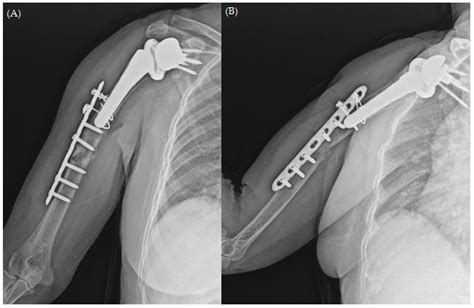

The Treatment of Periprosthetic Fracture Revision of the Humerus with ...